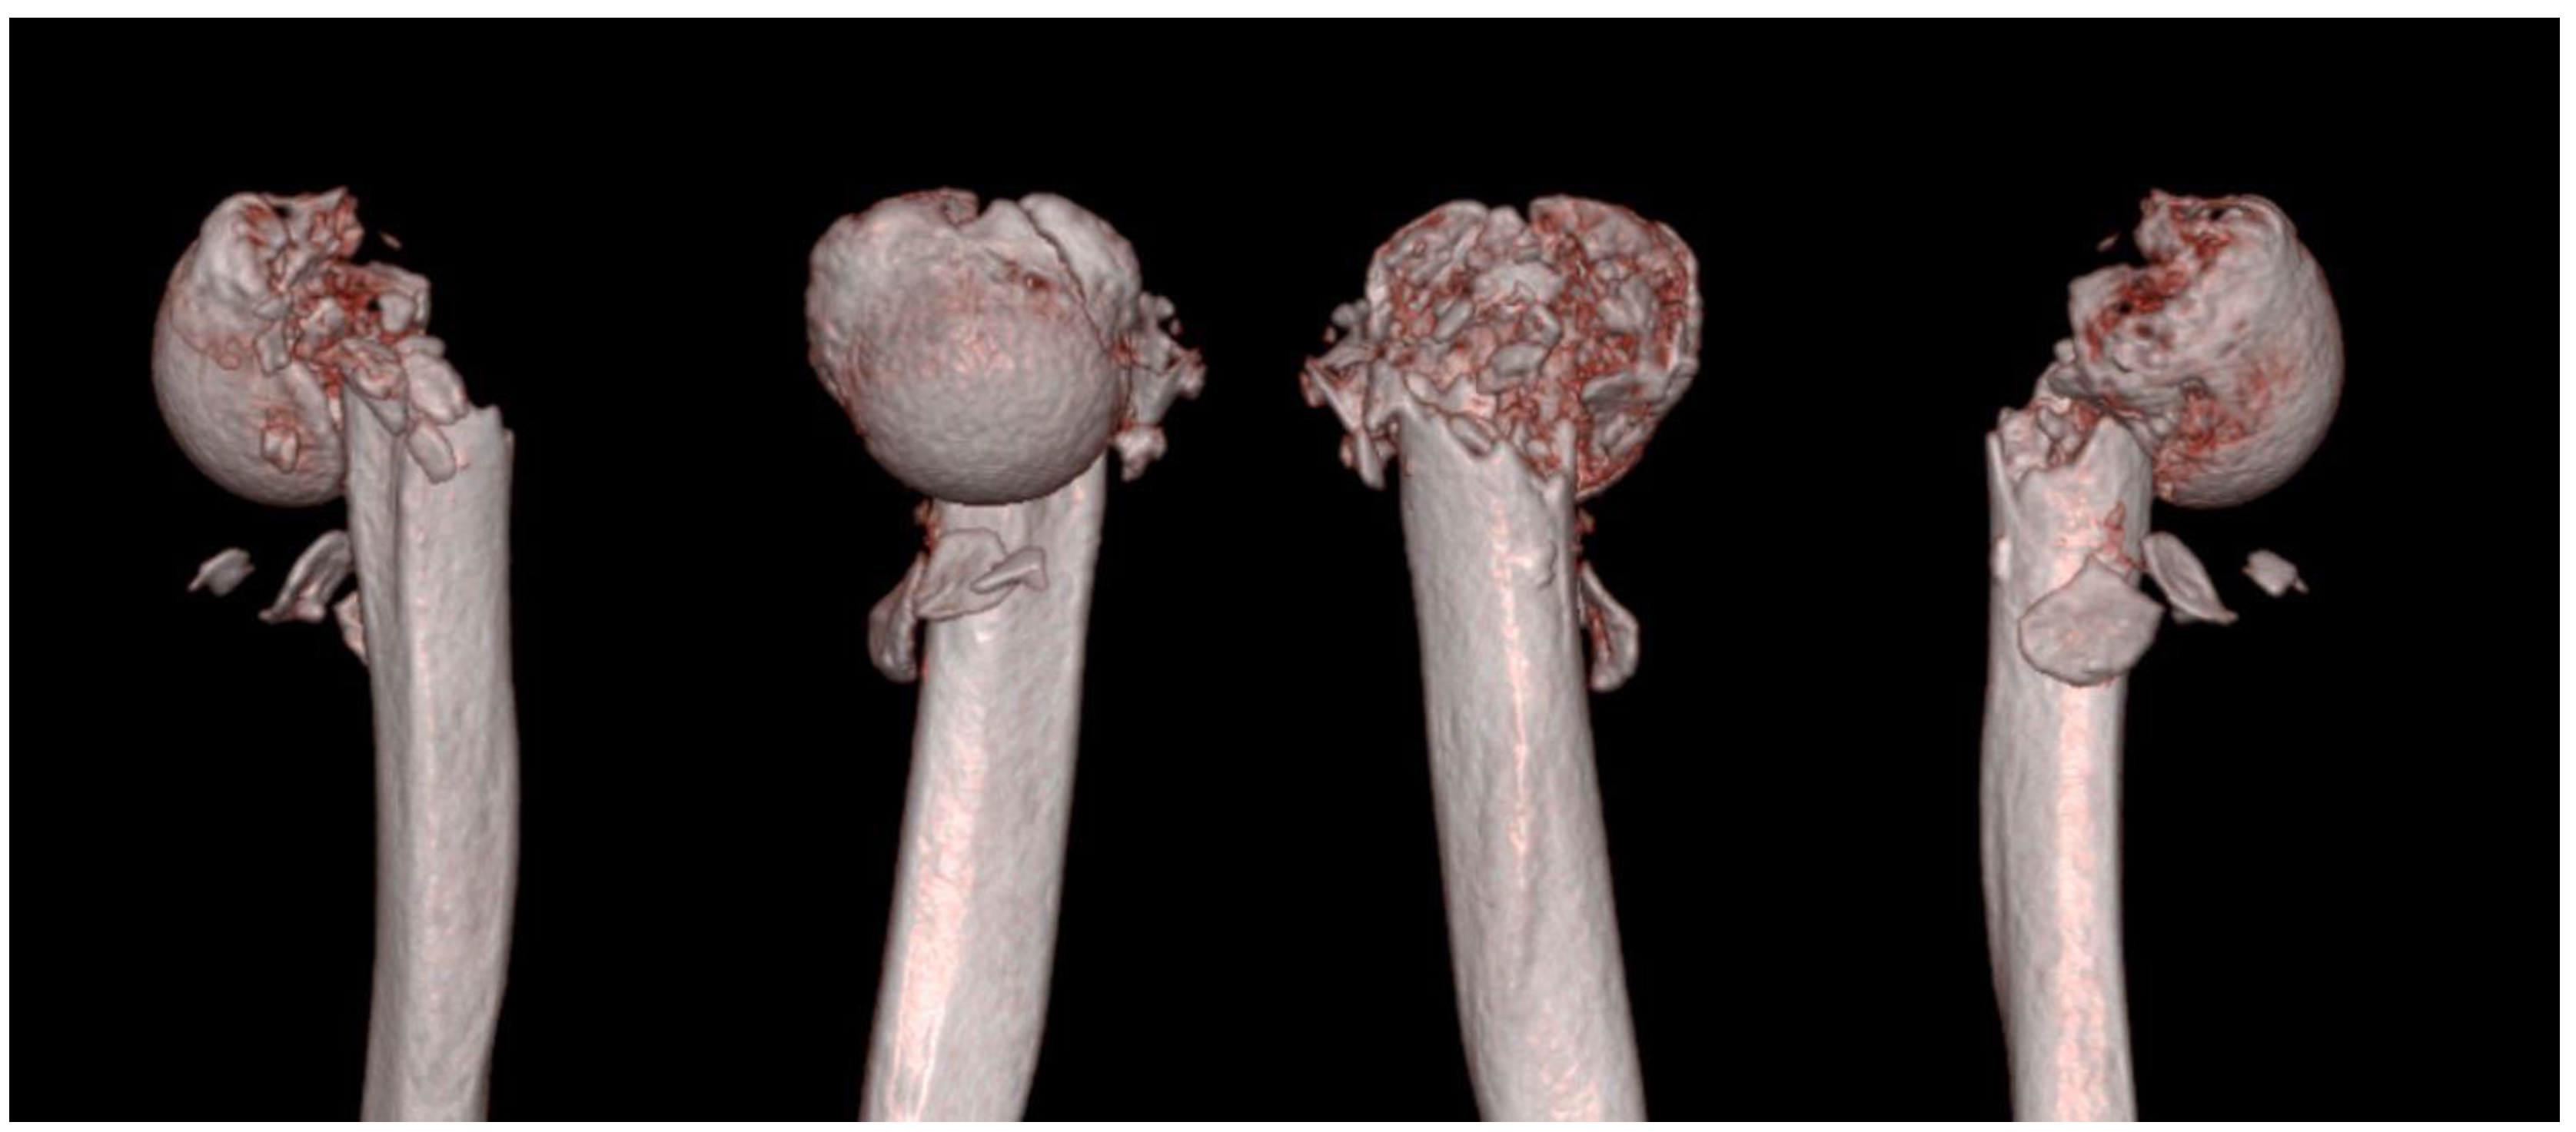

2. Case Presentation

Surgical Technique